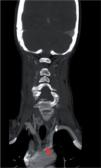

Figura 3.

Artéria vertebral direita anteriormente à apófise transversa de C4 (seta).